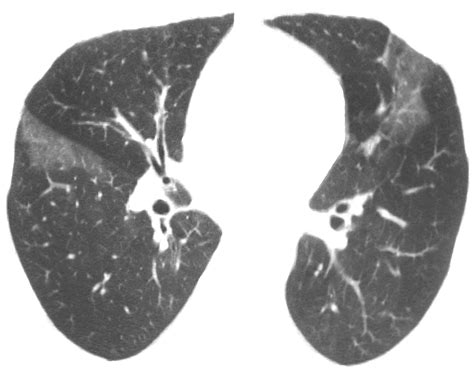

• Chest X-ray or CT scan

• bird fancier lung x ray

• bird fancier's lung radiology